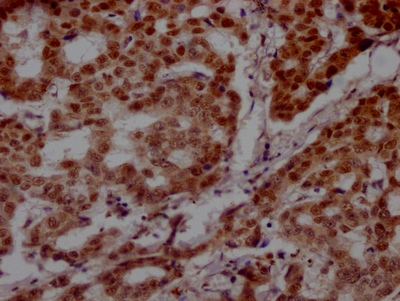

IHC image of CSB-RA160472A0HU diluted at 1:100 and staining in paraffin-embedded human breast cancer performed on a Leica BondTM system. After dewaxing and hydration, antigen retrieval was mediated by high pressure in a citrate buffer (pH 6.0). Section was blocked with 10% normal goat serum 30min at RT. Then primary antibody (1% BSA) was incubated at 4℃ overnight. The primary is detected by a Goat anti-rabbit IgG polymer labeled by HRP and visualized using 0.05% DAB.